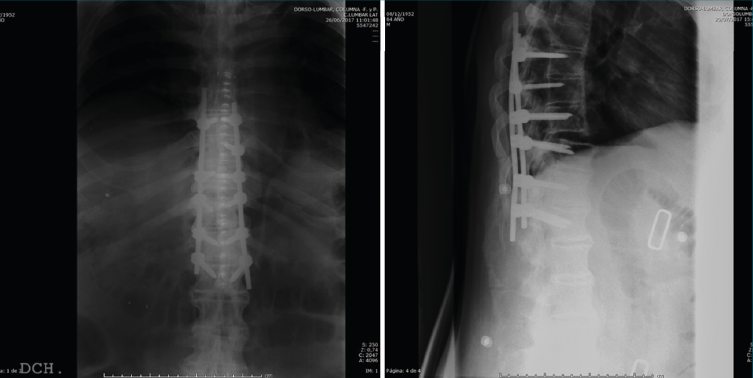

Con las consideraciones anteriores, lo operamos realizando una artrodesis instrumentada in situ T8/L1 bajo control neurofisiológico. Debemos reseñar que no pudimos navegar el tornillo derecho de T9 porque, a pesar de que parecía que estábamos correctamente posicionados en pedículo, el registro neurofisiológico detectaba que no.

figura6.png

Figura 6. Control postoperatorio.

Después de realizar un control radiológico postoperatorio (Figura 6), inició la deambulación con ortesis semirrígida dorsolumbar en el postoperatorio inmediato. Mantuvimos la ortesis durante 2 meses, iniciando la rehabilitación con una evolución clínica excelente.